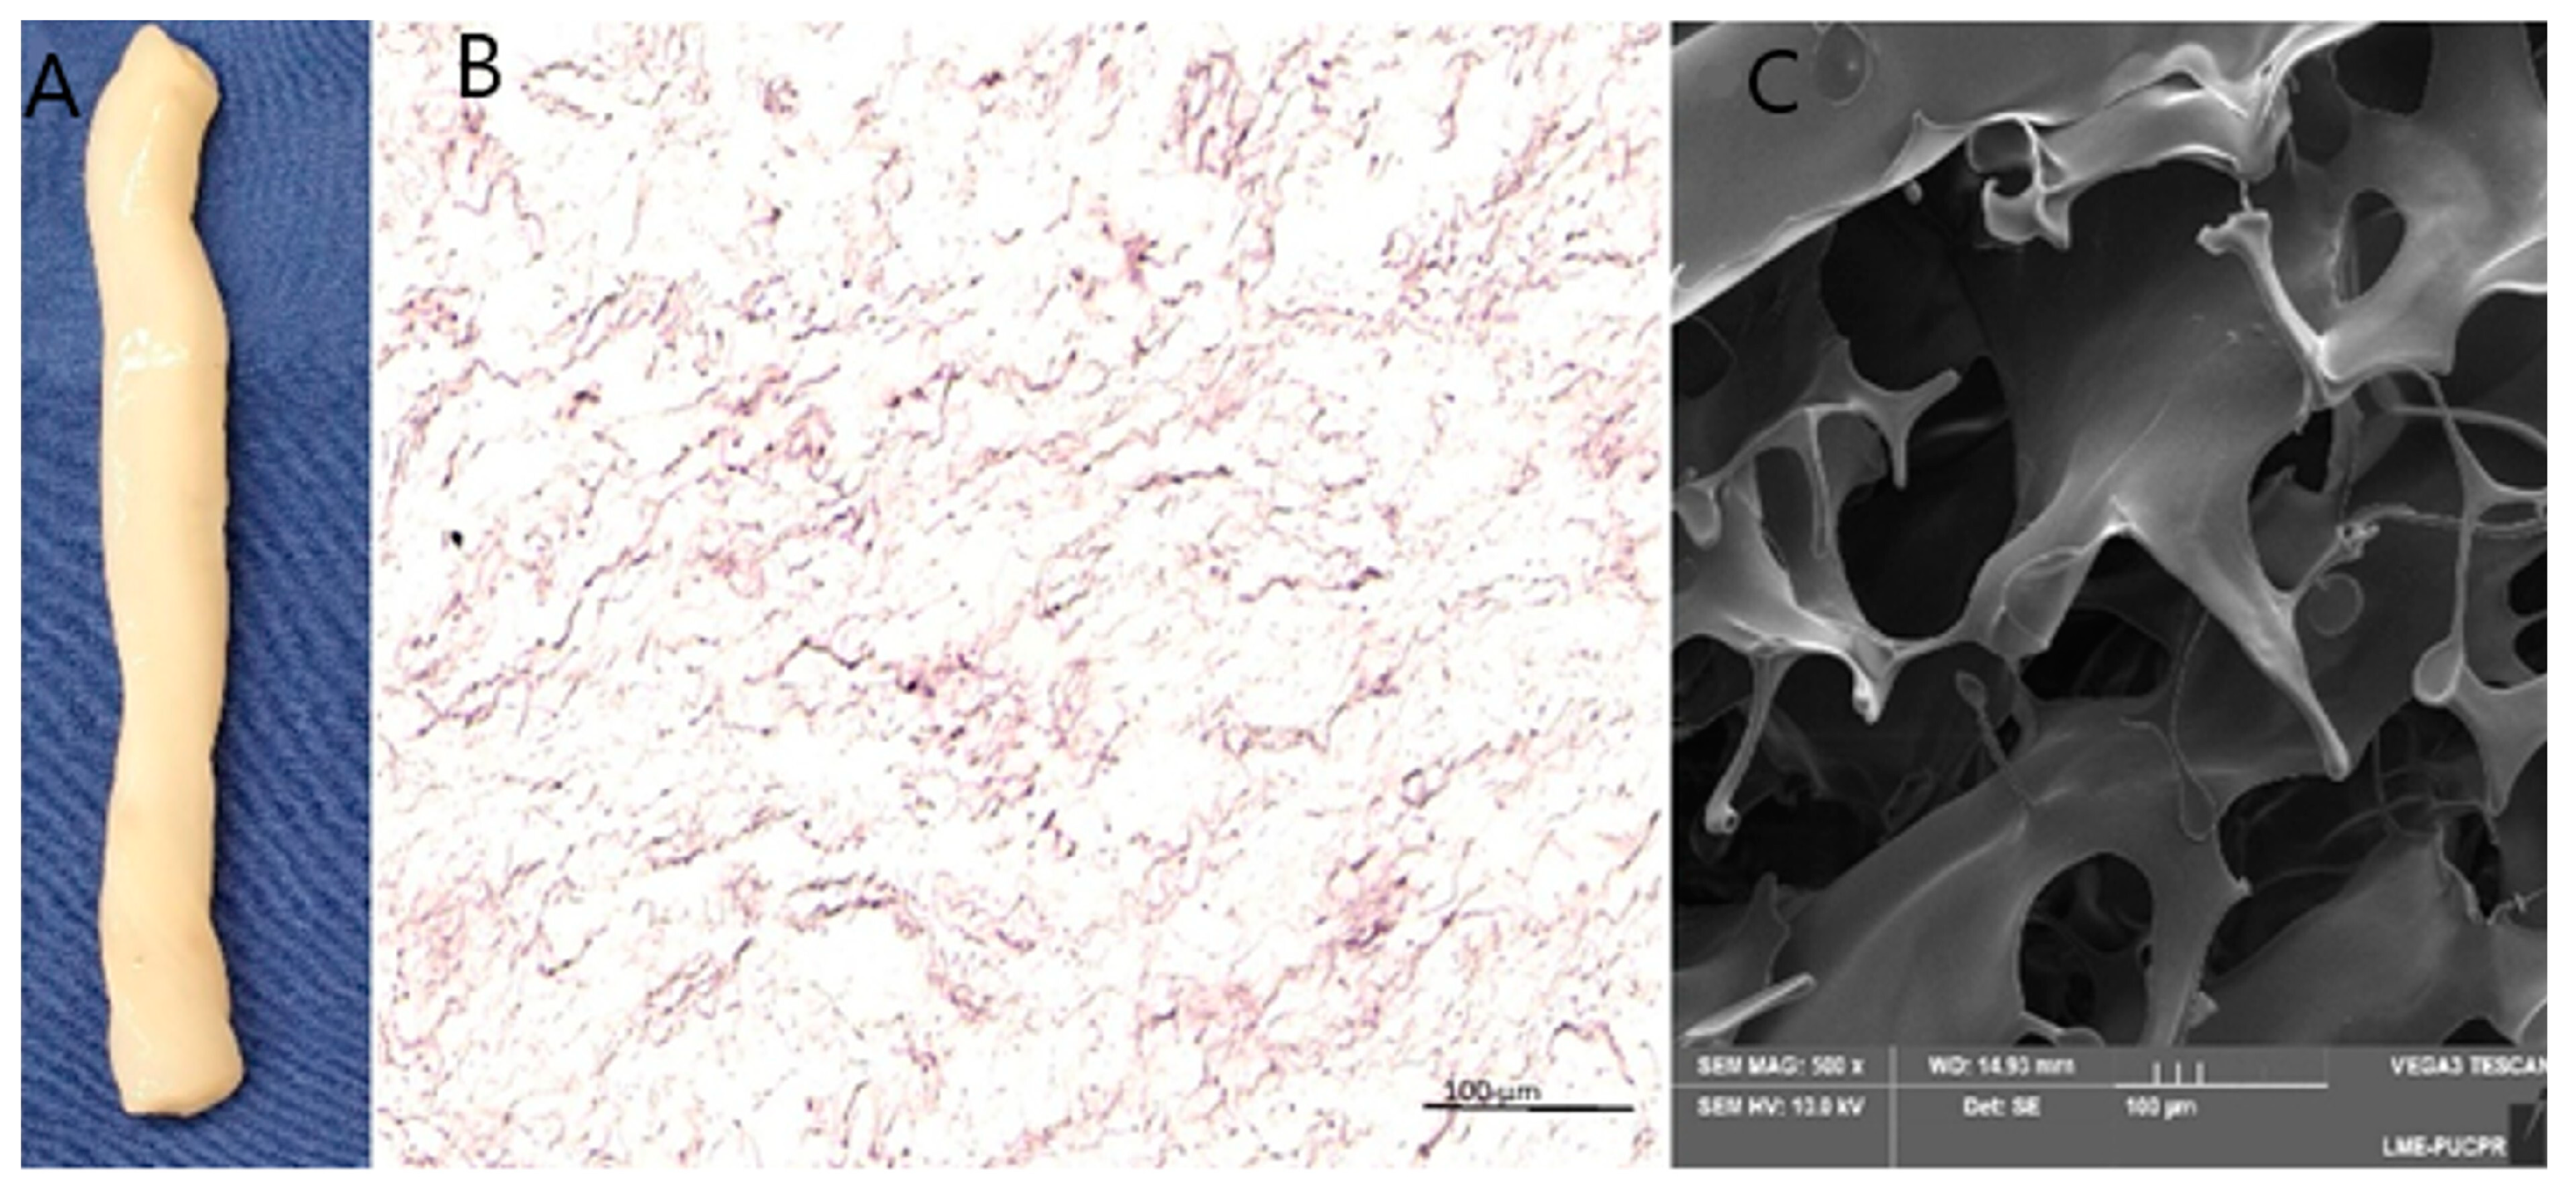

2.2. Preparation of Acellular Wharton’s Jelly (WJ)

2.7. Scanning Electron Microscopy

3.1. Tissue Characterization